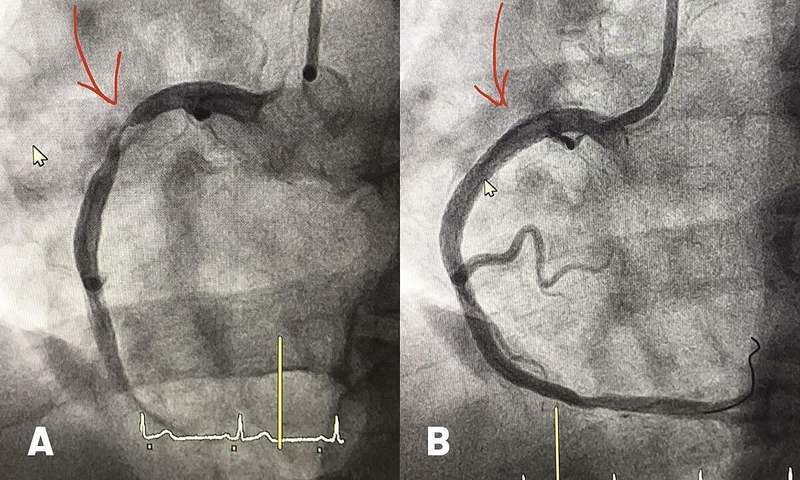

Trước khi bắt đầu đặt stent, bệnh nhân thường sẽ được hướng dẫn về quy trình và những yếu tố cần chuẩn bị trước, bao gồm việc không ăn không uống từ 6 đến 12 giờ trước quy trình. Khi bắt đầu, bác sĩ sẽ sử dụng một chất gây tê hoặc gây mê để đảm bảo sự thoải mái và không đau trong suốt quy trình. Sau khi bệnh nhân được tiêm chất gây tê, bác sĩ sẽ tiến hành xâm nhập vào động mạch vành thông qua một ống dẫn được chèn qua tĩnh mạch của cánh tay hoặc chân. Sử dụng các công cụ nhỏ và tinh tế, bác sĩ sẽ mở rộng động mạch vành bằng cách bơm bóng trong stent, giãn nở nó và đặt chúng vào nơi hẹp nhất của động mạch. Sau khi stent được đặt, một lớp thuốc chống viêm sẽ được phủ lên bề mặt của stent để giảm nguy cơ tái phát mảng xơ vữa.